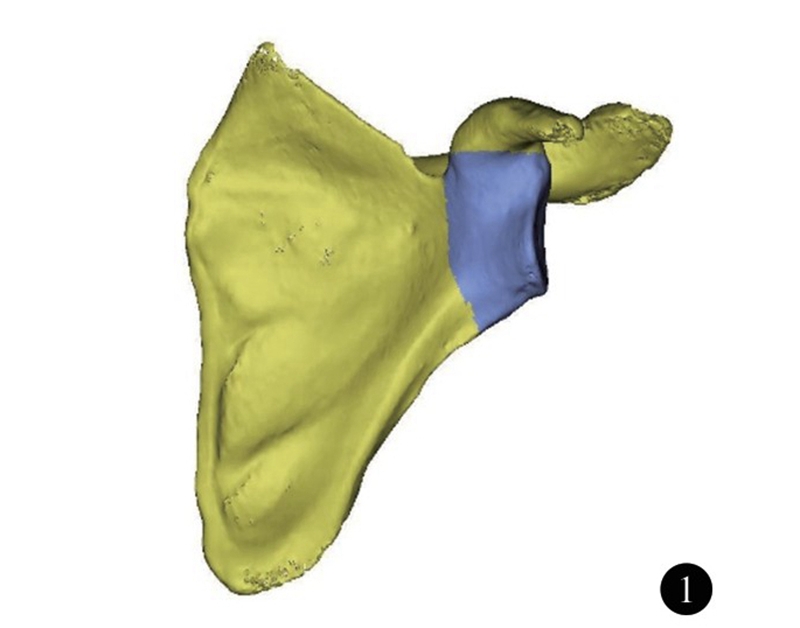

肩关节的活动主要由盂肱关节完成,为典型的球窝关节(杵臼关节) ,由肱骨头和肩胛盂构成。既往对肩关节的研究的重点集中在肩袖、关节囊韧带以及盂唇等结构,对肩关节的功能、稳定具有重要意义。随着中国社会老龄化的发展,肩胛盂骨性结构改变所带来的问题日趋严重,包括关节盂的缺损、退变。因此,了解肩胛盂的正常解剖结构,有助于对肩关节复杂损伤、疾病的治疗。肩胛盂的解剖结构包括肩胛盂关节面以及肩胛盂体部。肩胛盂体部(glenoid vault)是指肩胛骨包括肩胛盂表面及向内至肩胛冈外缘、喙突基底内缘的部分(图1)。这一区域骨量少,位置深,结构复杂。虽然传统尸体解剖研究可用于测量肩胛骨表面解剖学参数,但难以精确描述和测量,尤其是肩胛盂体部。随着电子计算机技术的不断发展和三维重建技术的进步,对肩胛盂骨性解剖结构的测量有了新的方法。研究肩胛盂骨性解剖学结构,可为肩胛盂内固定物和肩关节假体设计提供指导依据。

图1 肩胛盂体部形态(深色部分)示意图。包括肩胛盂表面及向内至肩胛冈外缘、喙突基底内缘的部分